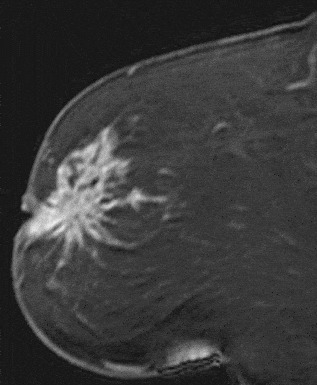

The shape and margins of masses can be described. Mass shape can be described as round (Fig. 2), oval (Fig. 3) or not otherwise specified (NOS). Margins of masses are smooth (Fig. 4), lobulated (Fig. 5), irregular (Fig. 6) or spiculated (Fig. 7). Spiculated or irregular masses are suspicious for carcinoma whereas a smooth margin is more suggestive of a benign lesion and lobulated borders are of intermediate concern. It is important to realize that margin analysis is dependent on spatial resolution and that even irregular borders can appear relatively smooth when insufficient resolution is used. Therefore, carcinoma may present with benign imaging features on MR imaging, particularly when small. In general, margin and shape analysis should be performed on the first post-contrast image to avoid washout and progressive enhancement of the surrounding breast tissue, which could obscure lesion analysis.

Figure 7. Spiculated mass. Pathology – Invasive lobular cancer.